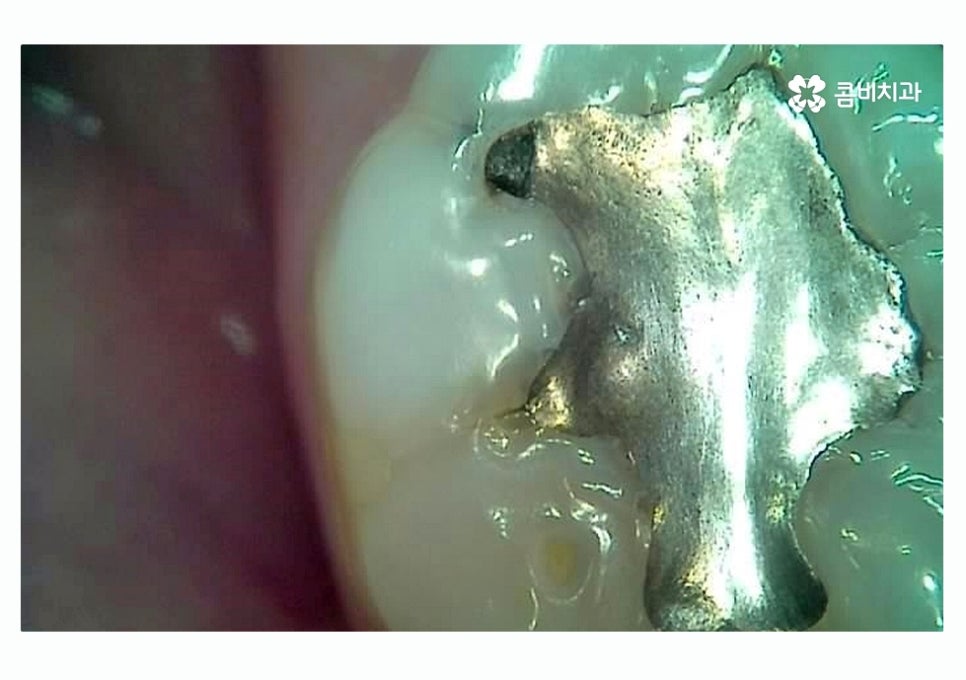

위 이미지에서 보이는 것처럼 이미 과거에

충치 떼우기 했던 부위에서 2차 충치가 생기는 사례는

치료 후 시간이 지날수록 주의해야 할 부분이라고 할 수 있어요.

이미 충치 치료를 했던 부위에 충치가 발생하는 이유는

치료 후에 시간이 지나면서 치아와 치료에 쓰인 재료 (레진, 아말감 등)

사이에 틈이 발생하거나 미세하게 크랙이 생기면서 2차 충치가

생길 수 있고 재료의 수명은 개인마다 차이가 있을 수 있기 때문에

정기적으로 검진을 받지 않으면 교체 시기를 놓치는 경우가 종종 있는데요.

재료의 수명이 다해 교체 시기를 놓친 경우

치아 내부에 충치가 생긴 경우가 많이 있어요.